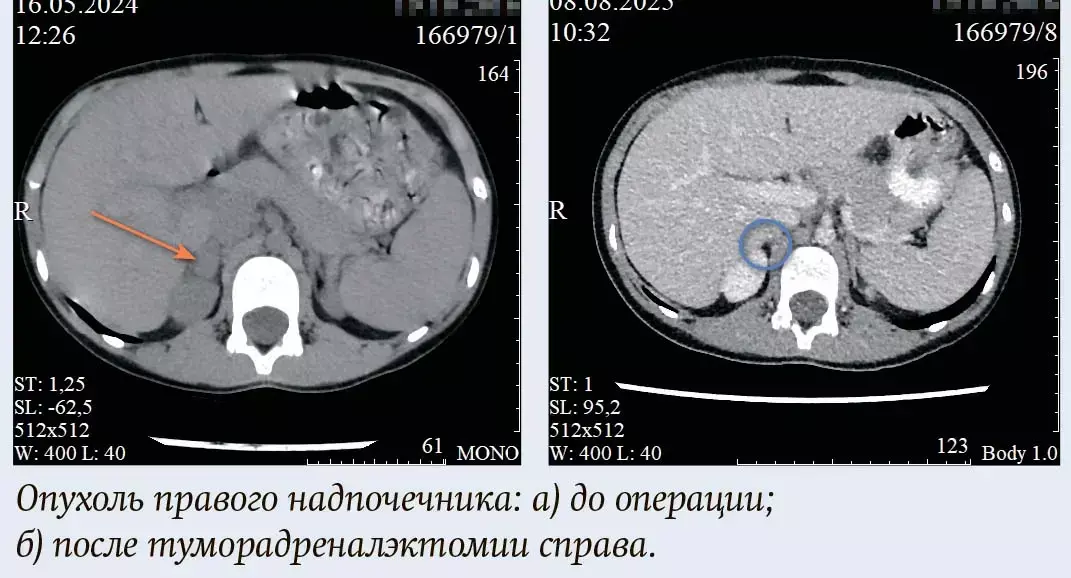

Пациентка, 8 лет, направлена в стационар РНПЦ ДОГИ для планового хирургического лечения. Из анамнеза: в 2022 году при плановом УЗИ органов брюшной полости случайно выявлено образование правого надпочечника диаметром около 1,5 см. В динамическом наблюдении в апреле 2024 года в анализах крови отмечено транзиторное повышение уровня кортизола и пролактина, что потребовало дообследования. Пациентка была консультирована эндокринологом и онкологом. Последующие гормональные исследования (май 2025) патологии не выявили. По данным инструментальной диагностики (КТ, МРТ) подтверждено наличие четко контурированного объемного образования правого надпочечника 16×15×11 мм. По результатам МРТ данные за аденому с низким содержанием жира. Принято решение о необходимости хирургической резекции образования.

Пациентке выполнена операция: диагностическая лапароскопия, туморадреналэктомия справа. Интраоперационных осложнений не было. Послеоперационный период протекал гладко. Состояние пациентки стабилизировалось в течение первых суток. Контрольное УЗИ органов брюшной полости на 6-е сутки после операции: свободной жидкости не выявлено. Заключительный гистологический диагноз: созревающая ганглионеврома. Пациентка была выписана в удовлетворительном состоянии на 6-е послеоперационные сутки.

Клиническое наблюдение иллюстрирует успешное применение лапароскопической техники для радикального удаления объемного образования надпочечника у ребенка.